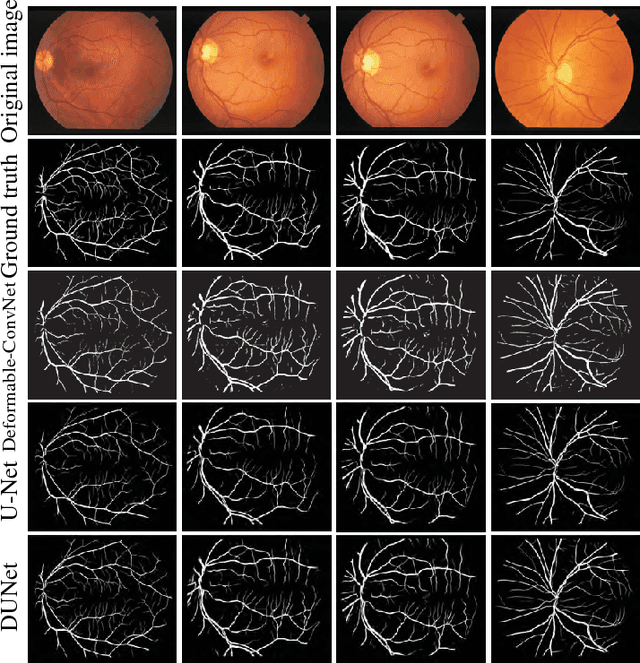

Abstract:Automatic segmentation of retinal vessels in fundus images plays an important role in the diagnosis of some diseases such as diabetes and hypertension. In this paper, we propose Deformable U-Net (DUNet), which exploits the retinal vessels' local features with a U-shape architecture, in an end to end manner for retinal vessel segmentation. Inspired by the recently introduced deformable convolutional networks, we integrate the deformable convolution into the proposed network. The DUNet, with upsampling operators to increase the output resolution, is designed to extract context information and enable precise localization by combining low-level feature maps with high-level ones. Furthermore, DUNet captures the retinal vessels at various shapes and scales by adaptively adjusting the receptive fields according to vessels' scales and shapes. Three public datasets DRIVE, STARE and CHASE_DB1 are used to train and test our model. Detailed comparisons between the proposed network and the deformable neural network, U-Net are provided in our study. Results show that more detailed vessels are extracted by DUNet and it exhibits state-of-the-art performance for retinal vessel segmentation with a global accuracy of 0.9697/0.9722/0.9724 and AUC of 0.9856/0.9868/0.9863 on DRIVE, STARE and CHASE_DB1 respectively. Moreover, to show the generalization ability of the DUNet, we used another two retinal vessel data sets, one is named WIDE and the other is a synthetic data set with diverse styles, named SYNTHE, to qualitatively and quantitatively analyzed and compared with other methods. Results indicates that DUNet outperforms other state-of-the-arts.